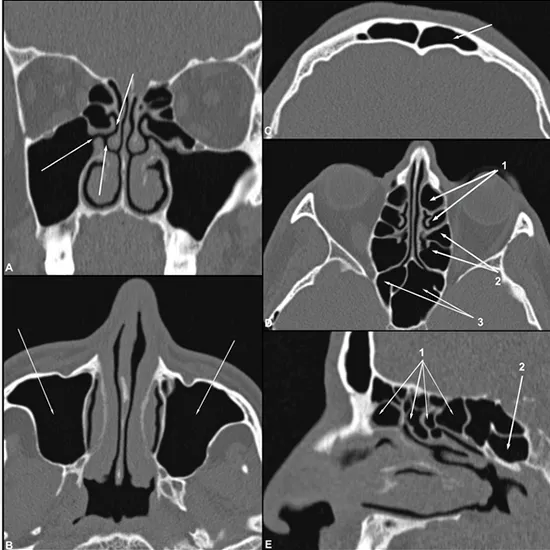

The following study seeks to evaluate whether the severity of chronic rhinosinusitis (CRS) is associated with obstructive sleep apnea (OSA) in adults with cystic fibrosis (pwCF).